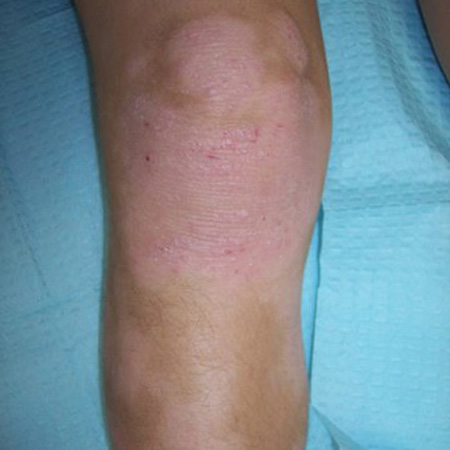

ბავშვებში, როგორც წესი, ჩართულია მომხრელი ზედაპირები, განსაკუთრებით მაჯები, კოჭები, იდაყვისა და მუხლქვეშა ფოსოები.[10][22]

მწვავე დაავადების დროს დაზიანებულ მიდამოებთან ერთად ქრონიკული ეგზემა ხშირად კისერს, ზურგსა და მკლავებს, ასევე მტევნებსა და ტერფებსაც აზიანებს.[1][7][64][Figure caption and citation for the preceding image starts]: მუხლქვეშა ფოსოს ლიქენიფიკაცია, ეგზემით დაავადებული ბავშვიFrom the personal collection of A. Hebert, MD; used with permission [Citation ends].

ლიქენიფიკაცია

ქრონიკული დერმატიტის ნიშანია სქელი, ლიქენიფიცირებული კანი.[49][Figure caption and citation for the preceding image starts]: მუხლქვეშა ფოსოს ლიქენიფიკაცია, ეგზემით დაავადებული ბავშვიFrom the personal collection of A. Hebert, MD; used with permission [Citation ends].